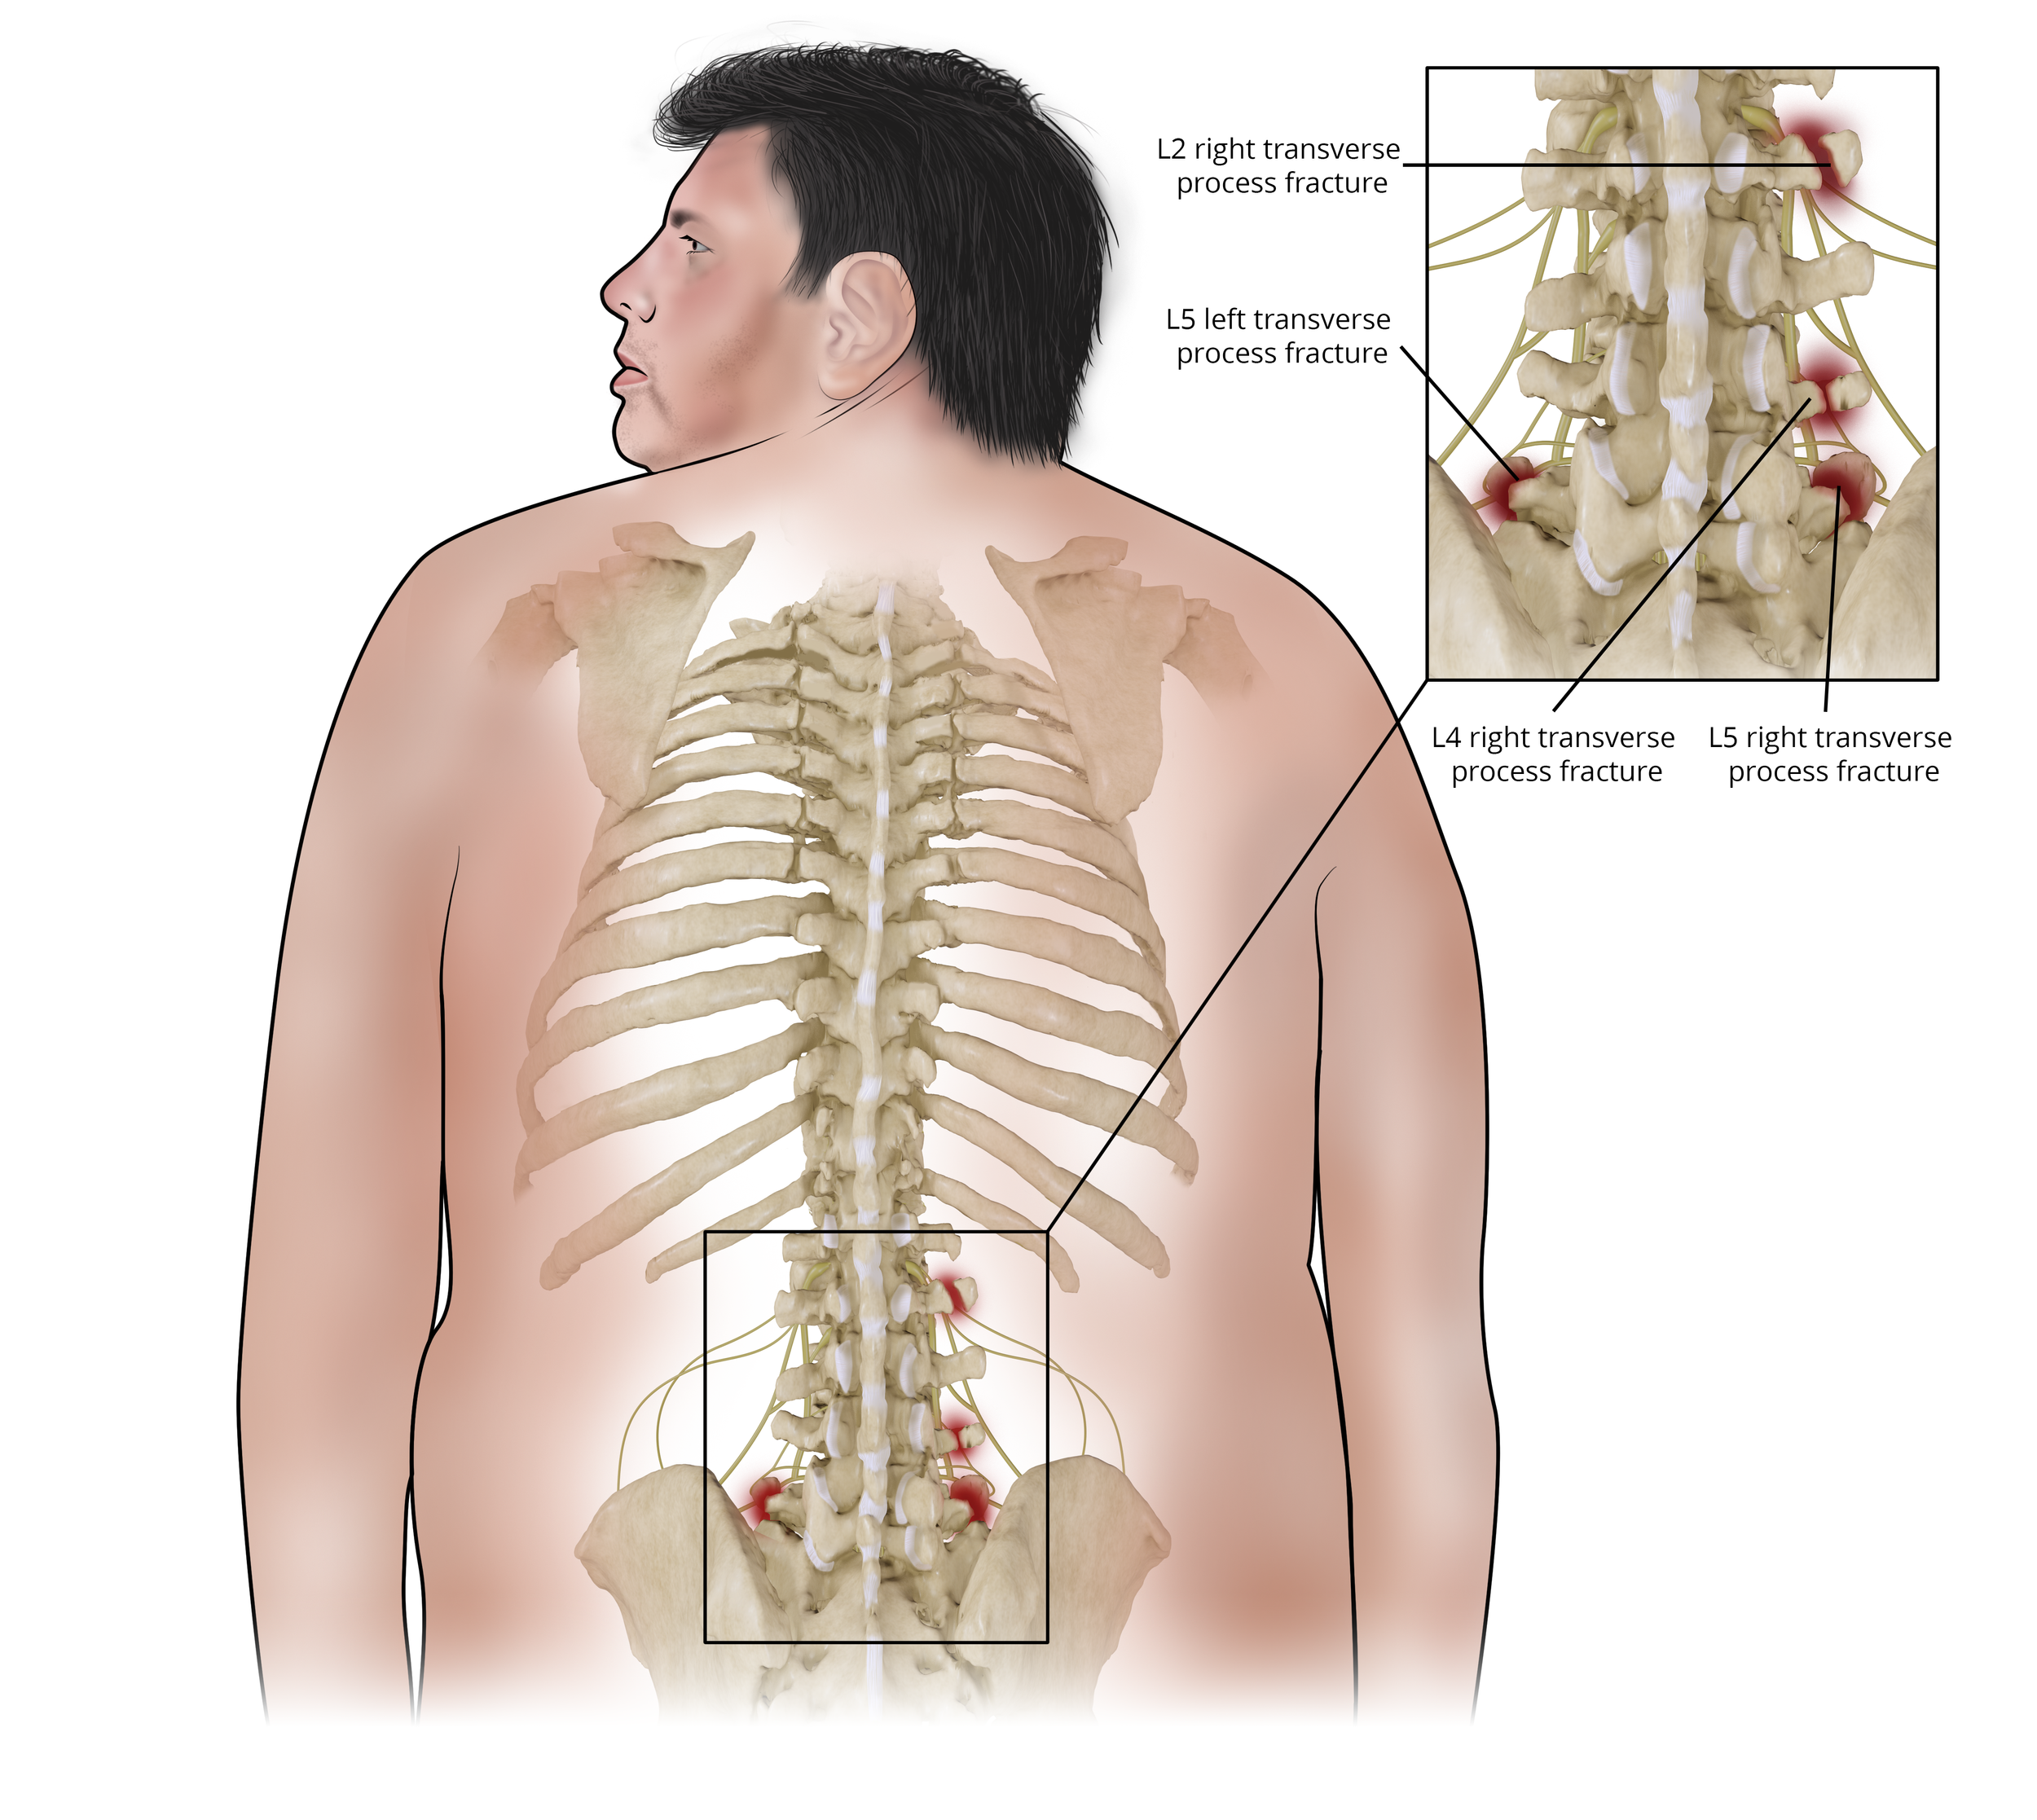

Transverse Process Fractures

Injuries sustained while unloading a tractor trailer.